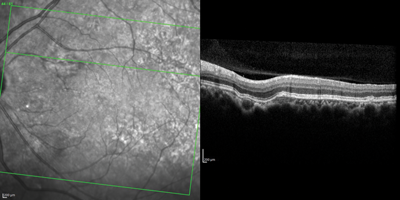

Figure 2: Aspect of fundus autofluorescence.

Figure 3: Aspect of SD optical coherence tomography.

2. What do Figures 2 and 3 show?

1. This shows pigmentary mottling in the affected area along with scattered drusen on the posterior pole. 2. Spectral domain optical coherence tomography (SD-OCT) shows unusual excavation of the choroid with outer retinal layers and retinal pigment epithelium (RPE) conformed with lesion excavation; the chorioscleral interface appears normal, without any ectasia or posterior staphyloma. Autofluorescence (AF) confirms the hypoautofluorescence in the area of choroidal lesion.